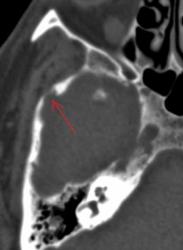

Метастазы в костях основания черепа.

Женщина средних лет с клиникой невралгии тройничного нерва справа. На КТ были выявлены округлые очаги деструкции в костях основания черепа (средней черепной ямки).

Наблюдение Nela.